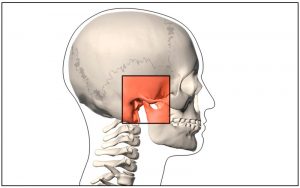

A crescente demanda de pacientes com Disfunção Temporomandibular sem atendimento especializado tem gerado, sistematicamente, diagnósticos imprecisos e tratamentos desnecessários ou iatrogênicos.

O curso de “Disfunção Temporomandibular para Ortodontistas” tem como objetivo gerar conhecimento ao ortodontista, de forma intensiva e direta, a respeito do diagnóstico e tratamento destas alterações, pautados na evidência que a literatura científica atual demonstra

Particularidades a respeito da possível interação entre a realidade clínica ortodontista e o potencial de causar, prevenir ou tratar DTM utilizando a ortodontia também serão abordados e desmistificados.